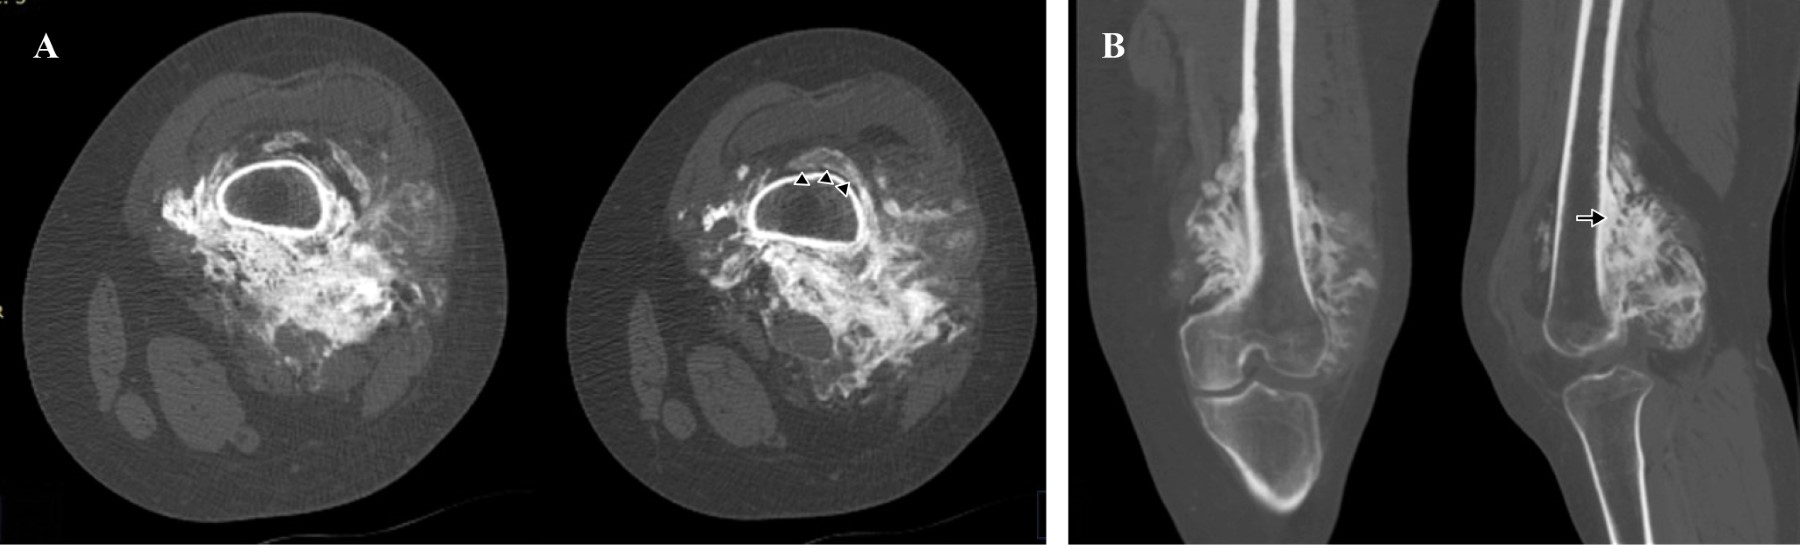

Introducción: el osteosarcoma parosteal convencional es un tumor óseo maligno poco común, que comprende el 4% de todos los osteosarcomas. Aunque es poco común, el osteosarcoma parosteal es el tipo más común de osteosarcoma de la superficie ósea. Presentamos las características clínicas, histológicas y de imagen de una variante histológica rara de un osteosarcoma parosteal, revisamos la literatura y enfatizamos la importancia de la correlación radio-patológica, así como la interpretación de una biopsia representativa para obtener el diagnóstico correcto. Reporte de caso: mujer de 36 años inició su cuadro un año antes de su ingreso al hospital con aumento de volumen en rodilla izquierda y dolor. Los estudios de imagen mostraron una tumoración heterogénea yuxtacortical localizada en la superficie posterior de la metáfisis femoral distal. Se realizó biopsia incisional, con diagnóstico de osteosarcoma parosteal y se realizó resección quirúrgica amplia. De acuerdo con los hallazgos de la pieza quirúrgica se realizó el diagnóstico de osteosarcoma parosteal con componentes de condrosarcoma y liposarcoma de bajo grado. El conocimiento de esta rara variante de osteosarcoma parosteal puede llevar a los ortopedistas oncólogos a considerar otros componentes y proporcionar márgenes quirúrgicos adecuados. Conclusión: presentamos las características clínicas, histológicas y de imagen de un osteosarcoma parosteal con componentes de liposarcoma y condrosarcoma de bajo grado.

Figura 3